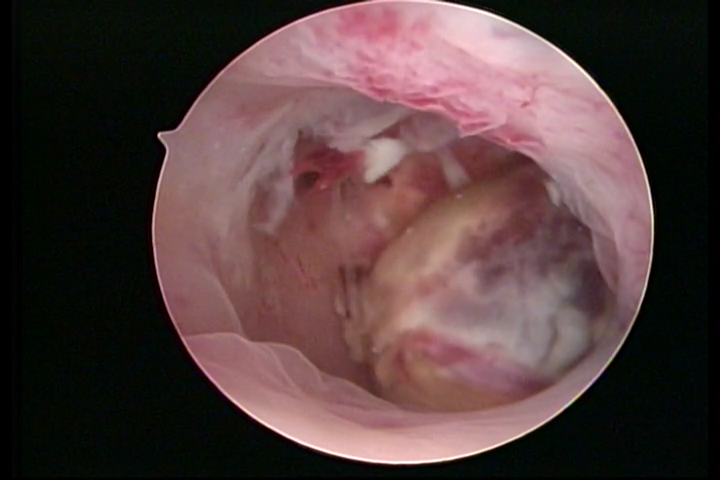

Osseous metaplasia and adenomyosis lesions